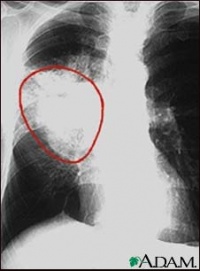

1、X线检查

X线检查是诊断肺癌最常用的重要手段。通过X线检查可以了解肺癌的部位和大小。早期肺癌病例X线检查虽尚未能显现肿块,但可能看到由于支气管阻塞引起的局部肺气肿、肺不张或病灶邻近部位的浸润性病变或肺部炎变。